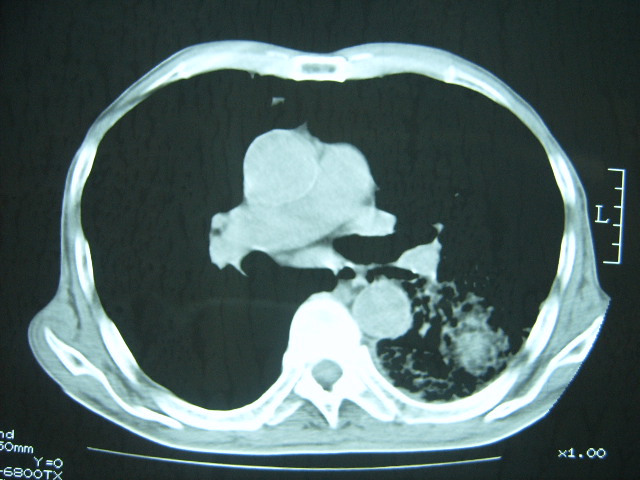

男74岁,咳嗽,寒战,低烧。有糖尿病史。

考虑:1、左下肺脓肿;

2、双肺结核。

考虑:糖尿病合并:1、左下肺炎继发肺脓肿;

考虑:1、左下肺脓肿;不排除霉菌感染

两肺结核,左下肺大片实变,内见空洞性病变,壁不规则,结合糖尿病史,考虑:结核性?霉菌性?建议结合实验室检查或治疗后复查。